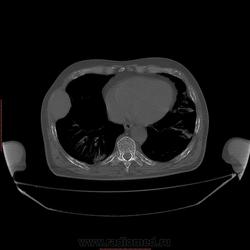

Пациент 1946 г.р., состоит на Д учете в онкодиспансере по поводу с-ч кожи (базалиома), прошел курс лучевой терапии, в 2009г на Ргенографии выявили образование 7 ребра, направили на Кт, на КТ (2009г) был выставлен д-з ГКО, пункционная биопсия не произведена. А сейчас вот такая картина, с множественными литическими очагами в костях грудного склета + образование 7 ребра, с отрицательной динамикой.

повторно взяли пациента, сняли кости таза, такая же картина- множественные очаги литической деструкции. Заключение: больше данных за миеломную болезнь.